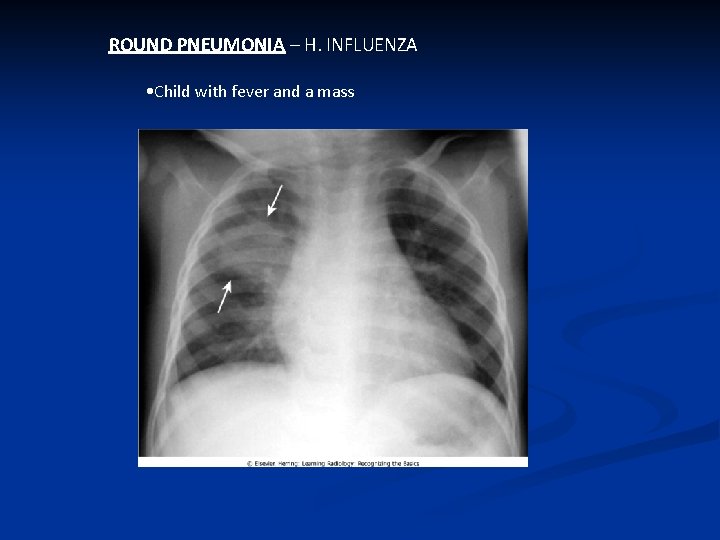

ROUND PNEUMONIA – H. INFLUENZA • Child with fever and a mass